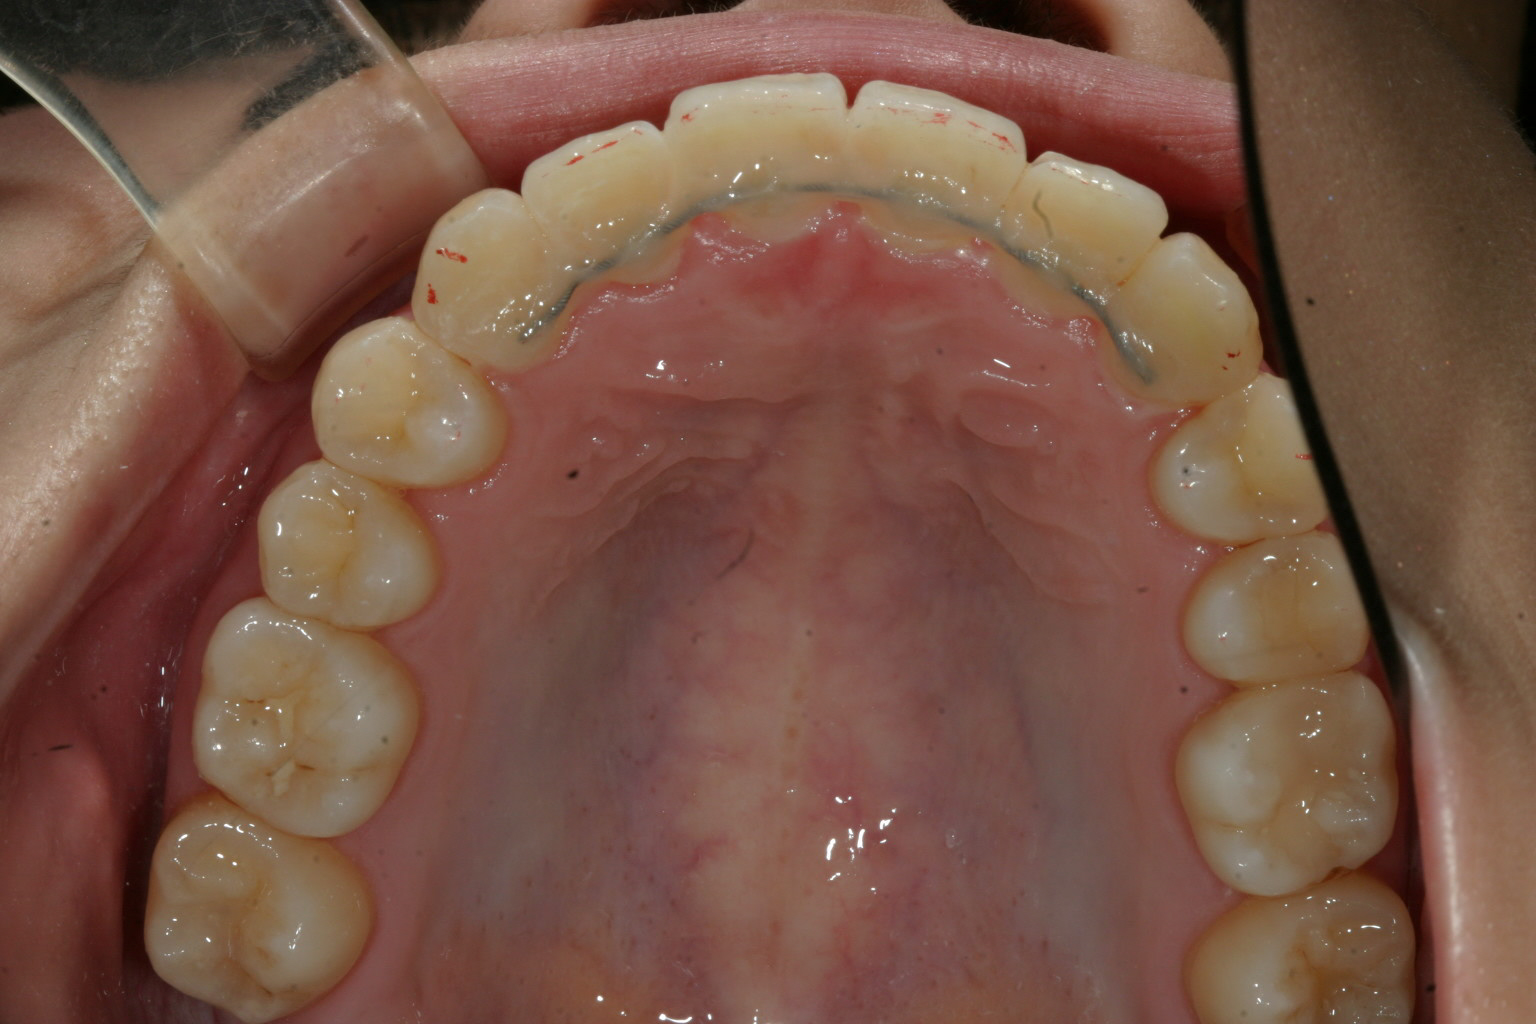

綺麗に改善出来ています。

下顎も前歯、臼歯綺麗になっています。

それで終わる場合とかみ合わせが今一しっくり噛んでない場合にはアップダウンエラスティックにて緊密な咬合を作ります。